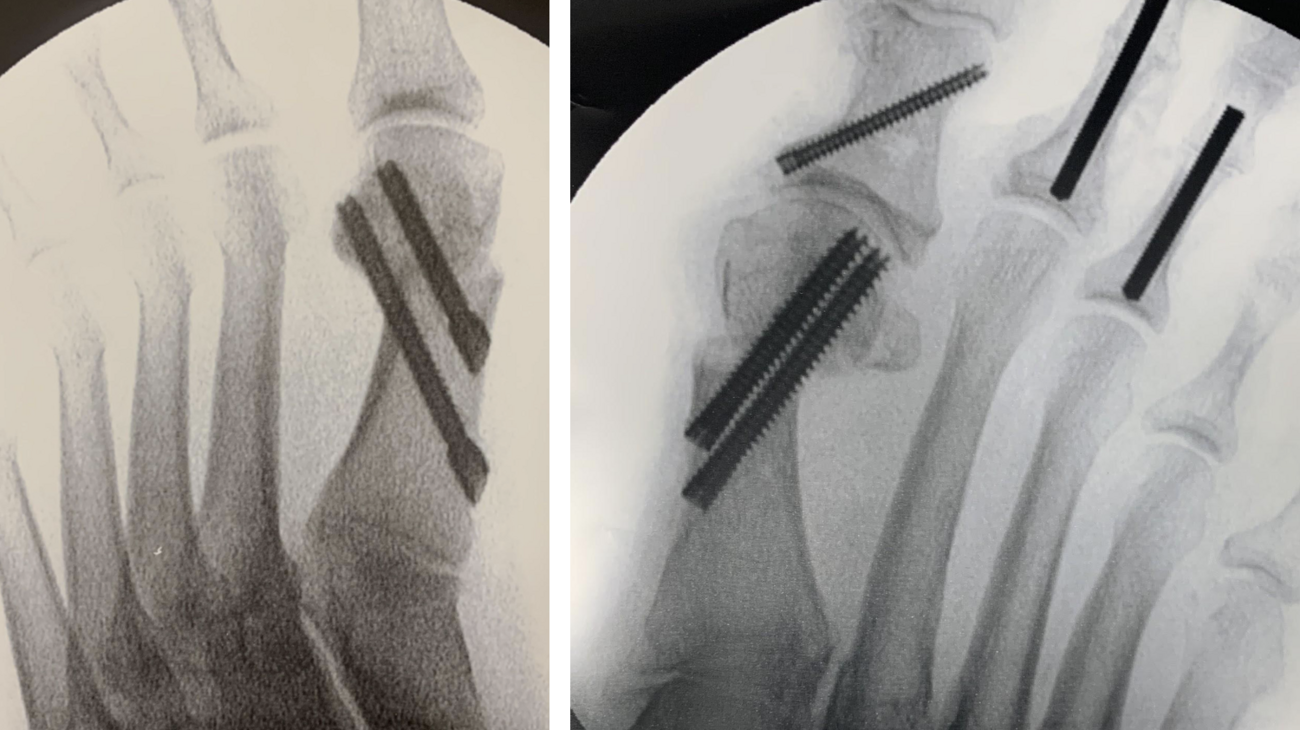

The surgeon may shift the capital fragment as much as necessary as long as there is some contact maintained between the metatarsal shaft and the head. It is possible to plan the amount of translation necessary on the preoperative X-ray, based on the position of the fibular sesamoid. In our experience, the lateral cortex of the metatarsal head should end up in a position just lateral to the fibular sesamoid on the preoperative X-ray. The gap between the lateral metatarsal head and metatarsal shaft will consolidate over time (see sixth and seventh photos above). A multitude of advanced options for fixation exist, including, but not limited to headless compression implants (see seventh and ninth photos above) and plate-intramedullary hybrid devices (see sixth photo above). Intramedullary devices do require a slightly larger incision for appropriate placement.